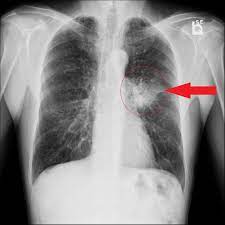

Left-sided pleural effusion

Chest X-ray with a left-sided pleural effusion

Blunted costophrenic angle Loss of sharp angle between diaphragm and chest wall.

Fluid layering Horizontal fluid level, more evident on erect or decubitus views.

Meniscus sign Crescent-shaped opacity rising higher laterally than medially at the lung base.